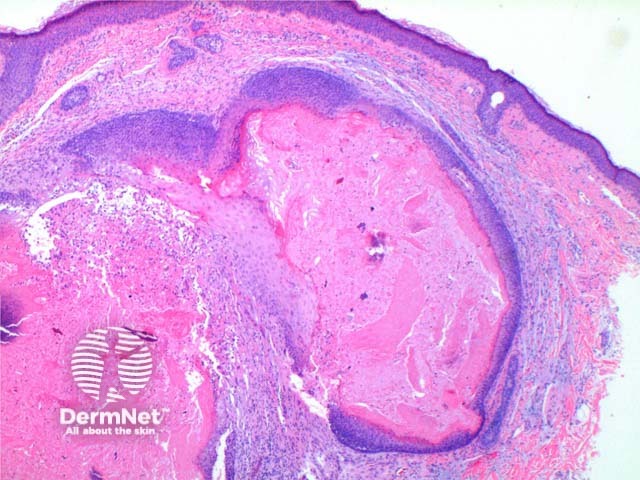

At low power the histological pattern seen in pilomatricoma is of a well-circumscribed nodulocystic tumour (Figure 2). While predominantly seen within the lower dermis, extension into the subcutaneous tissue is not uncommon. The tumour is comprised of a basaloid proliferation resembling the hair matrix cells, which matures into structureless eosinophilic cells lacking nuclei called shadow cells (Figures 3 and 4). The shadow cell area represents differentiation towards the hair cortex. Frequently there are areas of calcification within the shadow cell regions (Figure 5). A histiocytic infiltrate with multinucleated cells forms at sites of rupture (Figure 6).

Figure 2

Figure 3